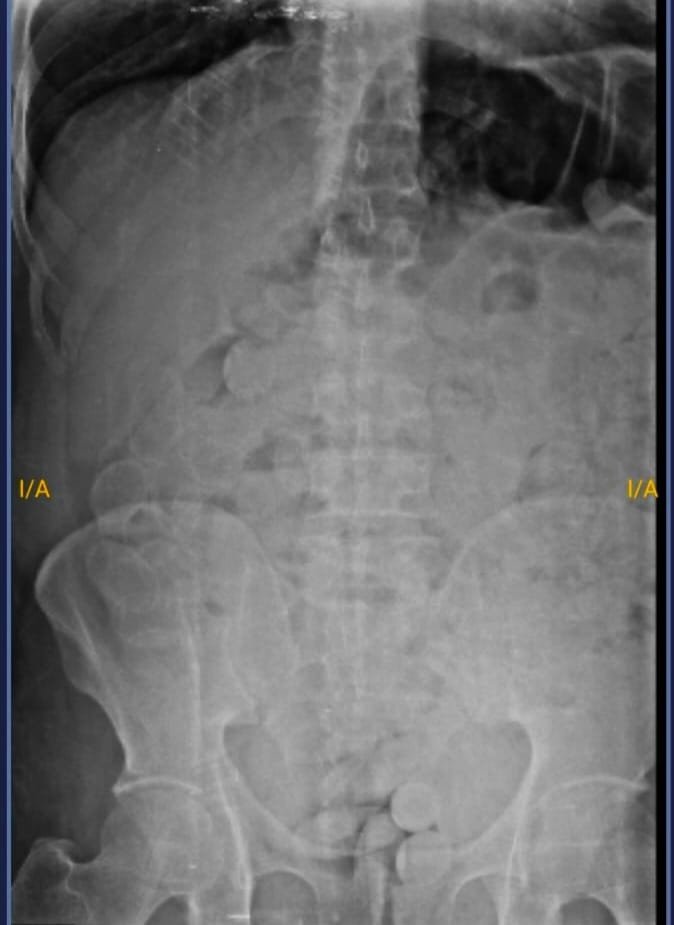

Ante esa situación, a los fines de preservar la salud de ambas personas, por orden de la Unidad Fiscal Federal de Jujuy, los involucrados fueron trasladados hasta el Nosocomio Jorge Uro de la ciudad de La Quiaca en donde les realizaron placas radiográficas y pudieron observar la presencia de cuerpos extraños.